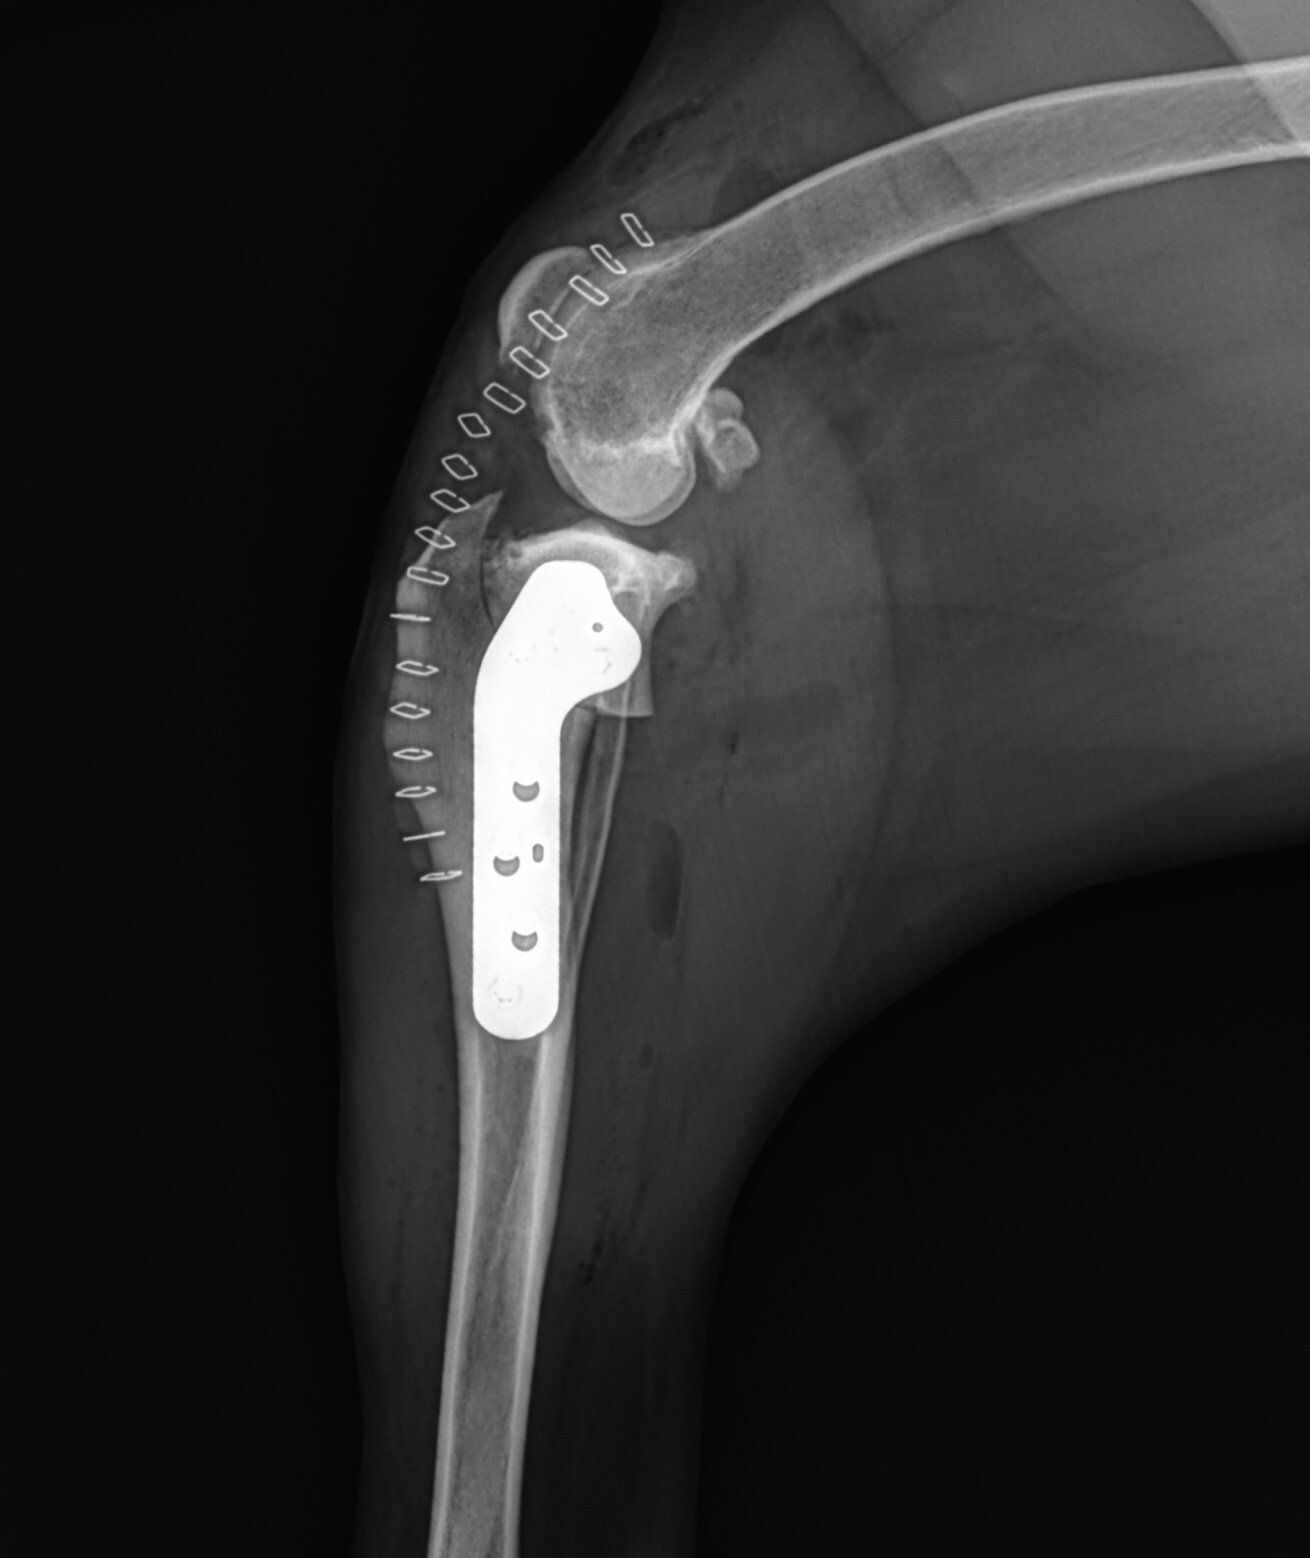

CBLO Surgery

The CBLO technique (CORA*Based Leveling Osteotomy), a state-of-the-art cruciate ligament repair based on the more widely known TPLO (Tibial plateau leveling osteotomy). The CBLO can have some advantages over the TPLO and other cranial cruciate ligament procedures depending on the patient. There are excellent short and long-term functional results. The CBLO can be performed on a juvenile patient because the surgery doesn’t involve the growth plate. The CBLO is also a preferred method on patients with excessive tibial slope that may require a wedge osteotomy during the repair. The TPLO and CBLO are both excellent procedures and are considered the “Gold Standard” for CCL repair.

Below are x-rays of just a few orthopedic surgeries before and after that Dr. Gose has performed.